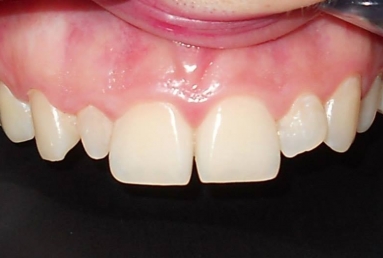

Very small lateral incisors covered with full ceramic crowns and ceramic veneers on central incisors. The prosthetic space was correctly split between the four incisors, in order to reduce the disproportion between the large centrals and the very small laterals. The preparation of the teeth was minimally invasive, all four incisors remained vital.